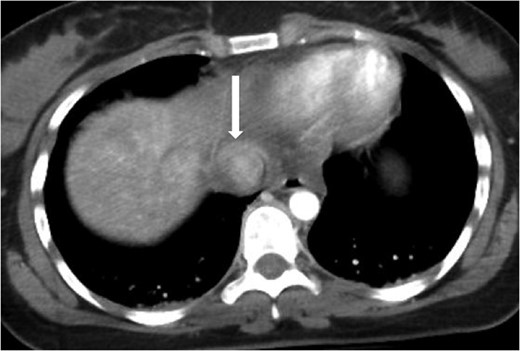

Axial contrast-enhanced CT of the abdomen performed 30 min after the initial CT of the chest showing persistence of the abnormal contour of the supradiaphragmatic IVC with contrast extravasation confined laterally and ventrally (arrow), nonexpanding pericaval hematoma.